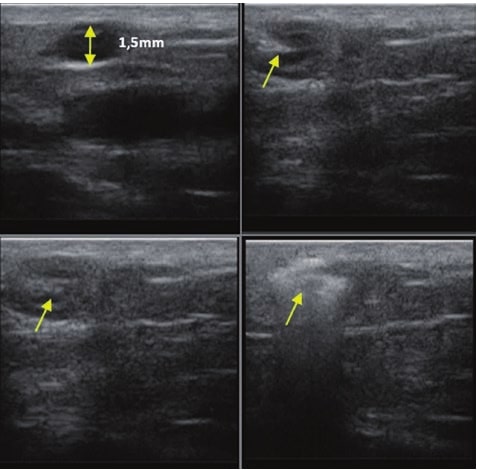

Die Doppler-Sonographie ermöglicht die Darstellung großer Gefäße und Perforatoren, die sich meist in tieferen Bereichen des subkutanen Gewebes befinden. Mit klassischem Ultraschall lassen sich kleinere Gefäße jedoch nicht darstellen. Für die Darstellung kleinerer Gefäße, die oberflächlich unter der Epidermis und im oberen subkutanen Gewebe liegen, wird HFU eingesetzt. Mit Sonden über 20 MHz Frequenz erhält man hochauflösende Ultraschallbilder, auf denen Objekte kleiner als 0,1 mm unterscheidbar sind. Mit zunehmender Auflösung nimmt jedoch die Eindringtiefe ab. Je nach Sonde und Gerät beträgt die maximale Eindringtiefe etwa 20–30 mm. Diese Eindringtiefe bei gleichzeitig hoher Bildauflösung ermöglicht die Beurteilung sehr kleiner Gefäße. HFU erlaubt die genaue Bestimmung des Verlaufs und der Lage kleiner Gefäße in der Haut, was entscheidend für die Wahl der Verschlussmethode und die Planung des Eingriffs ist. Oft sind an der Hautoberfläche nur wenige Gefäße sichtbar – erst durch die Ultraschalluntersuchung lässt sich die tatsächliche Anzahl und der Verlauf feststellen. Für einen erfolgreichen Verschluss muss das gesamte Gefäß behandelt werden, nicht nur der sichtbare Teil, da sonst eine schnelle Rekanalisation erfolgt (7). Häufig ändert das an der Haut sichtbare Gefäß seinen Verlauf, wird gewundener und zieht in tiefere Hautschichten (8). HFU ermöglicht zudem die Darstellung der Perforatoren zwischen kleinen Gefäßen und die Messung grundlegender Parameter wie Durchmesser, Wandstärke, Tiefe und Blutfluss (6). Mit der 40-MHz-Sonde von Ultrasonix kann auch der Blutfluss mittels Farbdoppler visualisiert werden.

Sklerotherapie verschließt Gefäße durch Injektion eines chemischen Obliterans. Sie ist kostengünstig und relativ einfach durchzuführen. Hauptsächlich für retikuläre Venen >3 mm, kann aber auch bei kleineren Gefäßen eingesetzt werden (10). Bei Gefäßen <3 mm ist die Punktion schwierig, wodurch Komplikationen wahrscheinlicher werden (7). HFU hilft hier, den Gefäßverlauf exakt darzustellen und den Eingriff unter Ultraschallkontrolle durchzuführen, wodurch das Risiko einer Nekrose durch Fehlinjektion minimiert wird. HFU überwacht zudem die Wirksamkeit des Eingriffs.

Dieses Verfahren überträgt intravaskuläre Techniken aus der Behandlung großer oberflächlicher Venen auf die Mikroebene. Ein Laserfaser wird in das Gefäß eingeführt und koaguliert das Gefäß mit Laserenergie (7,11). HFU ist für die korrekte Durchführung unerlässlich, da es Verlauf, Anatomie, Faserposition, Koagulation und Erfolg des Eingriffs überwacht.